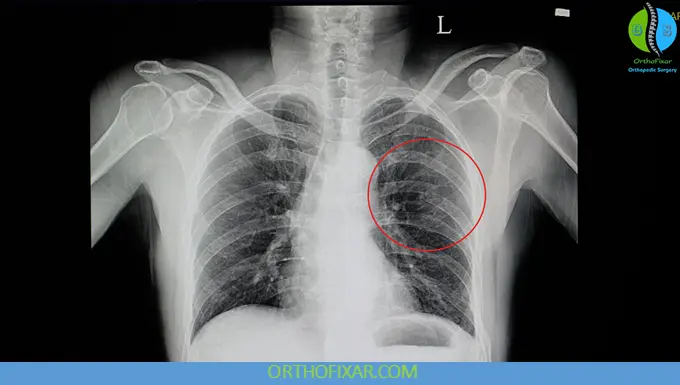

- Chest X-ray (AP view):

- Initial imaging in trauma

- Detects some fractures and complications (e.g., pneumothorax)

- Rib series:

- May improve fracture detection

- CT scan:

- Most sensitive modality

- Indicated when:

- Suspecting associated injuries

- Evaluating lung parenchyma

- Planning surgical fixation

CT should not be performed solely to diagnose rib fractures without clinical indication.